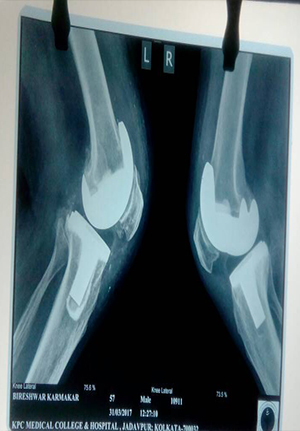

Total Knee Replacement

before operation

After operation